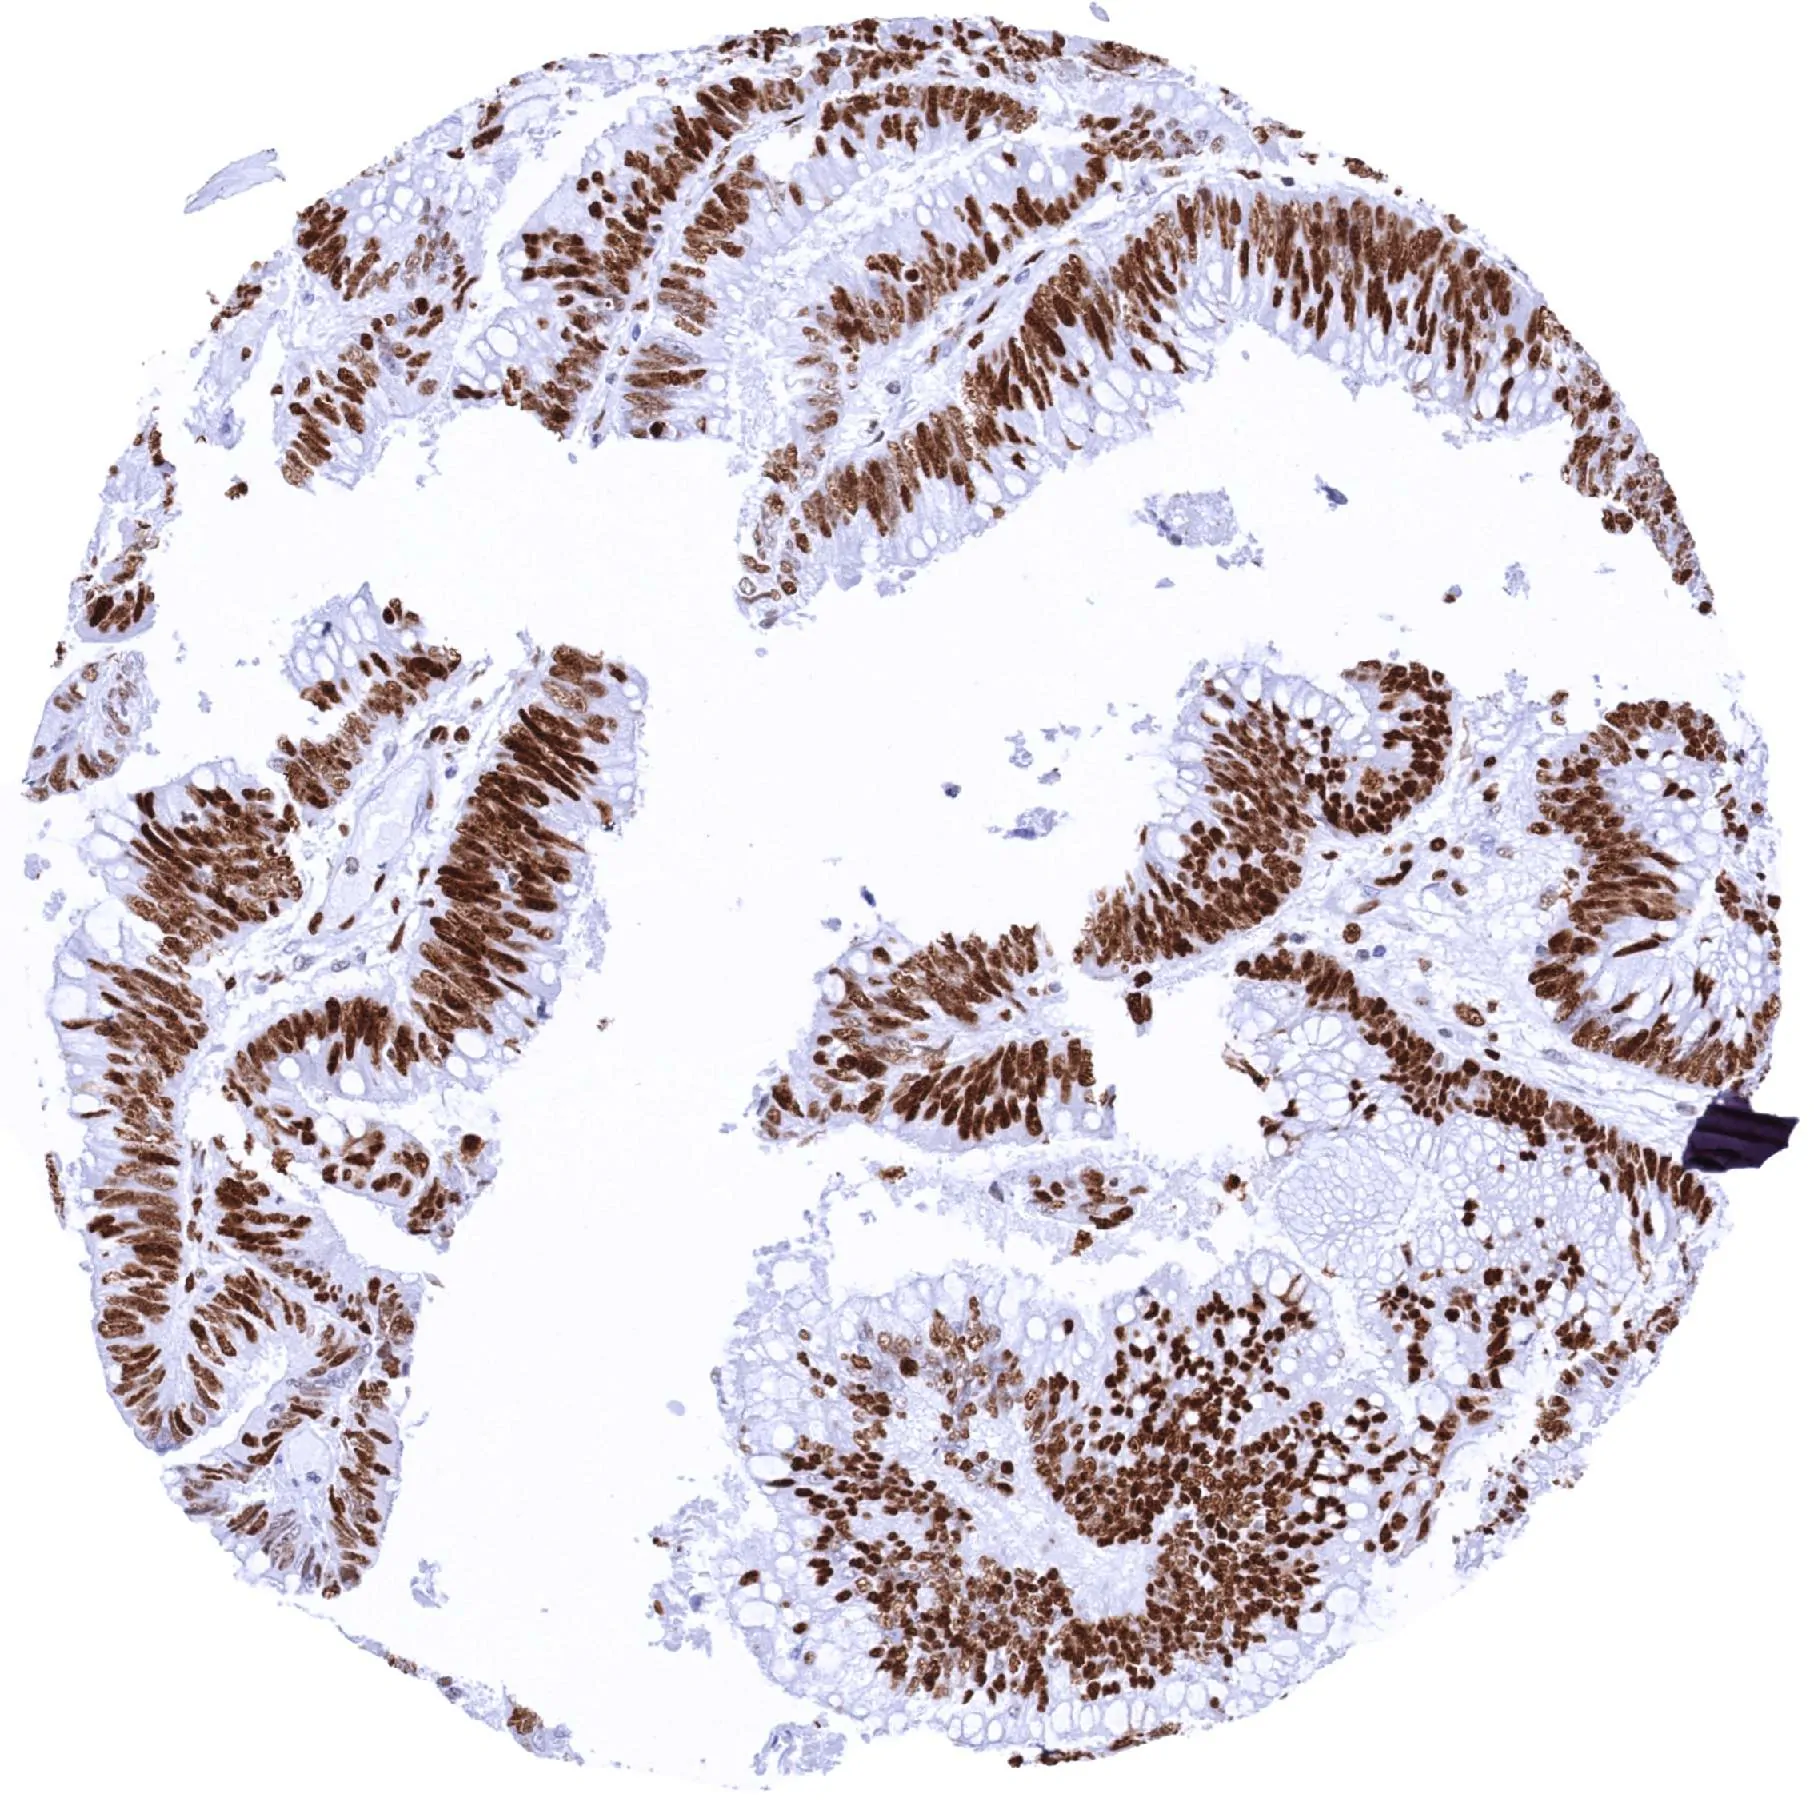

Colon – Colorectal adenocarcinoma with moderate to strong MCM2 staining of most tumor cells